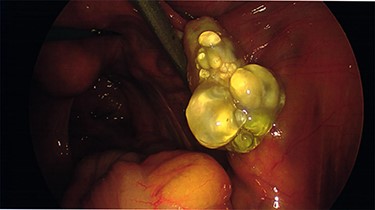

Intraoperative findings were inconsistent with all pre-operative ultrasound diagnoses. Both ovaries appeared suspicious for malignancy with cystic lesions covering the surface of the right, while the left appeared to contain two smaller cysts (Figs 3–5). There were no hydrosaplinges or free fluid within the pelvis. Given the abnormal features of the ovaries, the surgeon proceeded with the laparoscopic BSO without spillage. Pelvic washings were performed, though there were no atypical peritoneal or omental lesions for biopsy.

The intra-operative photographs of the posterior aspect of the right ovary.

The case emphasizes the diagnostic importance of histopathology, particularly in the setting of unanticipated and sinister macroscopic findings. The macroscopic appearances of the ovaries suggested malignancy diagnosis; however, the histopathology identified benign epithelial cysts [15]. The cyst lining was comprised of a single layer of epithelial cells amid normal ovarian stroma (Figs 6 and 7). The cysts contained normal serous epithelium with cilia lining the cyst lumen. These histological findings are consistent with the Müllerian phenotype and are therefore endosalpingiosis, ectopic tubal cell deposits on the surface of the ovaries, not that of hydrosalpinges or malignant ovarian cysts as the diagnostic rollercoaster suggested [15].